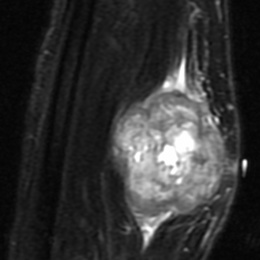

An example of an Leiomyosarcoma MRI is shown.